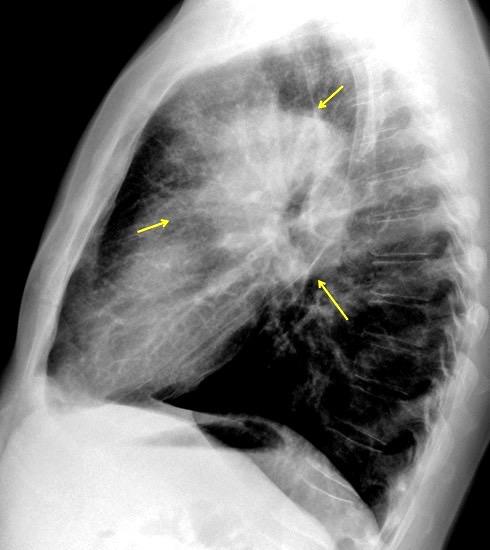

Líneas paraespinales formando un “paréntesis” por encima del diafragma. El signo señala el origen “intratorácico” de la lesión.

Conrad A et al. Pott’s disease associated with large and multiple abscesses in a 30-year-old migrant from Chad. BMJ Case Rep 2018

(lesiones toracoabdominales) La divergencia de las líneas paraespinales apunta a lesión toracoabdominal, que desde el tórax desciende y penetra en el abdomen.

Signo del “iceberg” positivo en Tb vertebral

Afectación por vía hematógena. Región dorsolumbar más frecuente. Afectación inicial: irregularidad de los platillos vertebrales, disminución del disco intervertebral con esclerosis ósea adyacente. Kim. Radiographics.2001